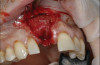

8. Tooth No. 8 with diagnosis of Grade III socket, requiring extraction followed by guided bone regeneration and a rotated pedicle flap to gain hard and soft tissue for future implant placement.

Figure 8

9. Tooth No. 8 with diagnosis of Grade III socket, requiring extraction followed by guided bone regeneration and a rotated pedicle flap to gain hard and soft tissue for future implant placement.

Figure 9

10. Tooth No. 8 with diagnosis of Grade III socket, requiring extraction followed by guided bone regeneration and a rotated pedicle flap to gain hard and soft tissue for future implant placement.

Figure 10

11. Tooth No. 8 with diagnosis of Grade III socket, requiring extraction followed by guided bone regeneration and a rotated pedicle flap to gain hard and soft tissue for future implant placement.

Figure 11